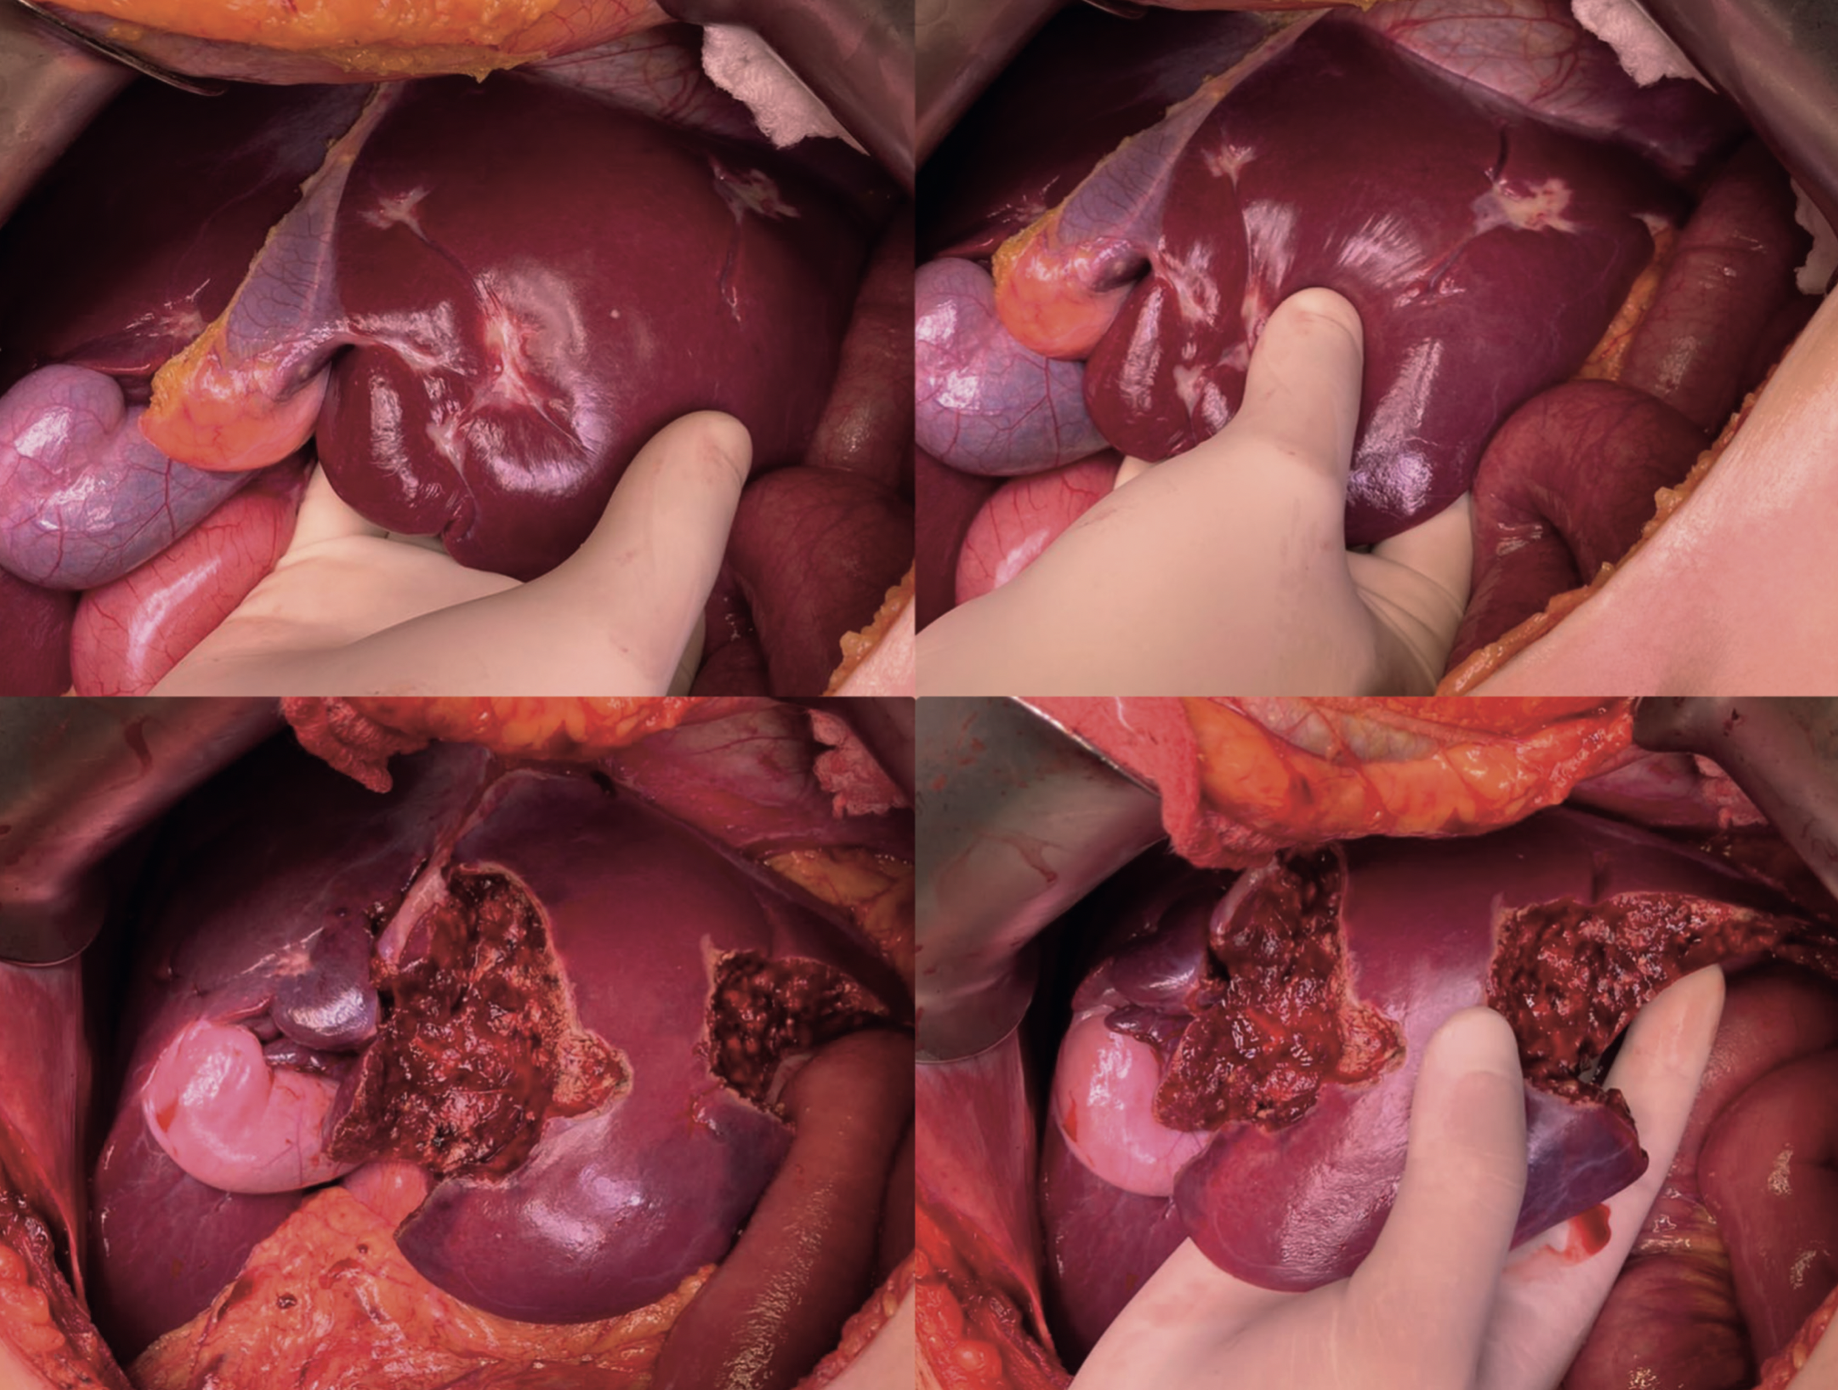

Gabriela Susana Ochoa Suazo, Nicolas Jarufe Cassis, Martin Dib Marambio

|

|

|